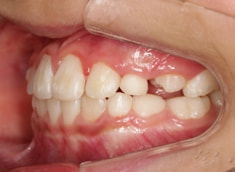

小児期ケース:反対咬合(受け口)

治療法:上顎拡大装置+フルパッシブブラケット(クリアスナップ)+フェイスマスク等

治療期間:1年3ヶ月

解説:上顎の急速拡大により、骨格的に拡大、前方牽引を促します。

治療前